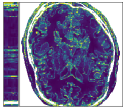

Figure 3 shows an example of a single frame of the reconstructed MR image sequences for an acceleration factor of using several approaches. We show the reconstructions that correspond to the single scalar parameter as well as to the scalar parameter pair (one spatial and one temporal) which are the parameters that maximize the PSNR of entire cine MR image and are obtained via a grid search by making use of the corresponding ground truth image. We also show the results that correspond to the parameters and which are respectively the single and the pair of scalar parameters that on average maximize the PSNR over the training set. These were obtained by treating the scalar regularization parameters as trainable parameters and training them by minimizing (33). We finally show the results for our estimated parameter-map with the proposed method. As observed, for all choices of the regularization parameters, the error with respect to the target image was significantly reduced compared to the initial zero-filled reconstruction. Further, we can see how the use of the estimated parameter-map yields the most accurate reconstruction and the best preservation of image details.

Figure 4 summarizes the results obtained over the test set with the help of box-plots. Compared to the initial zero-filled reconstruction, an improvement is clearly visible for all choices of the regularization parameter with respect to all reported measures and for all acceleration factors. In addition we see how allowing the temporal direction to be differently regularized than the two spatial dimensions positively influences the results compared to having one global parameter (orange vs blue). Last, we see how using the proposed method to estimate an entire spatio-temporal parameter-map further surpasses the scalar regularization parameter-maps (green vs orange and blue), especially in terms of SSIM. Table 1 lists the mean and the standard deviation of all TV-reconstructions. The results are consistent with the ones from the box-plots.

Figure 5 shows an example of a spatio-temporal regularization parameter-map which was estimated using the proposed approach for an acceleration factor of . The network estimates the regularization parameter-map to be pointwise relatively consistenly higher than the spatially required regularization. This result is in fact expected as the temporal dimension is the one for which the gradients of the images are the sparsest because of the high temporal correlation. Further, we see how the network consistently predicts both the spatial regularization as well as the temporal regularization to be less strong in the area where most of the movement is expected, i.e. in the cardiac region.